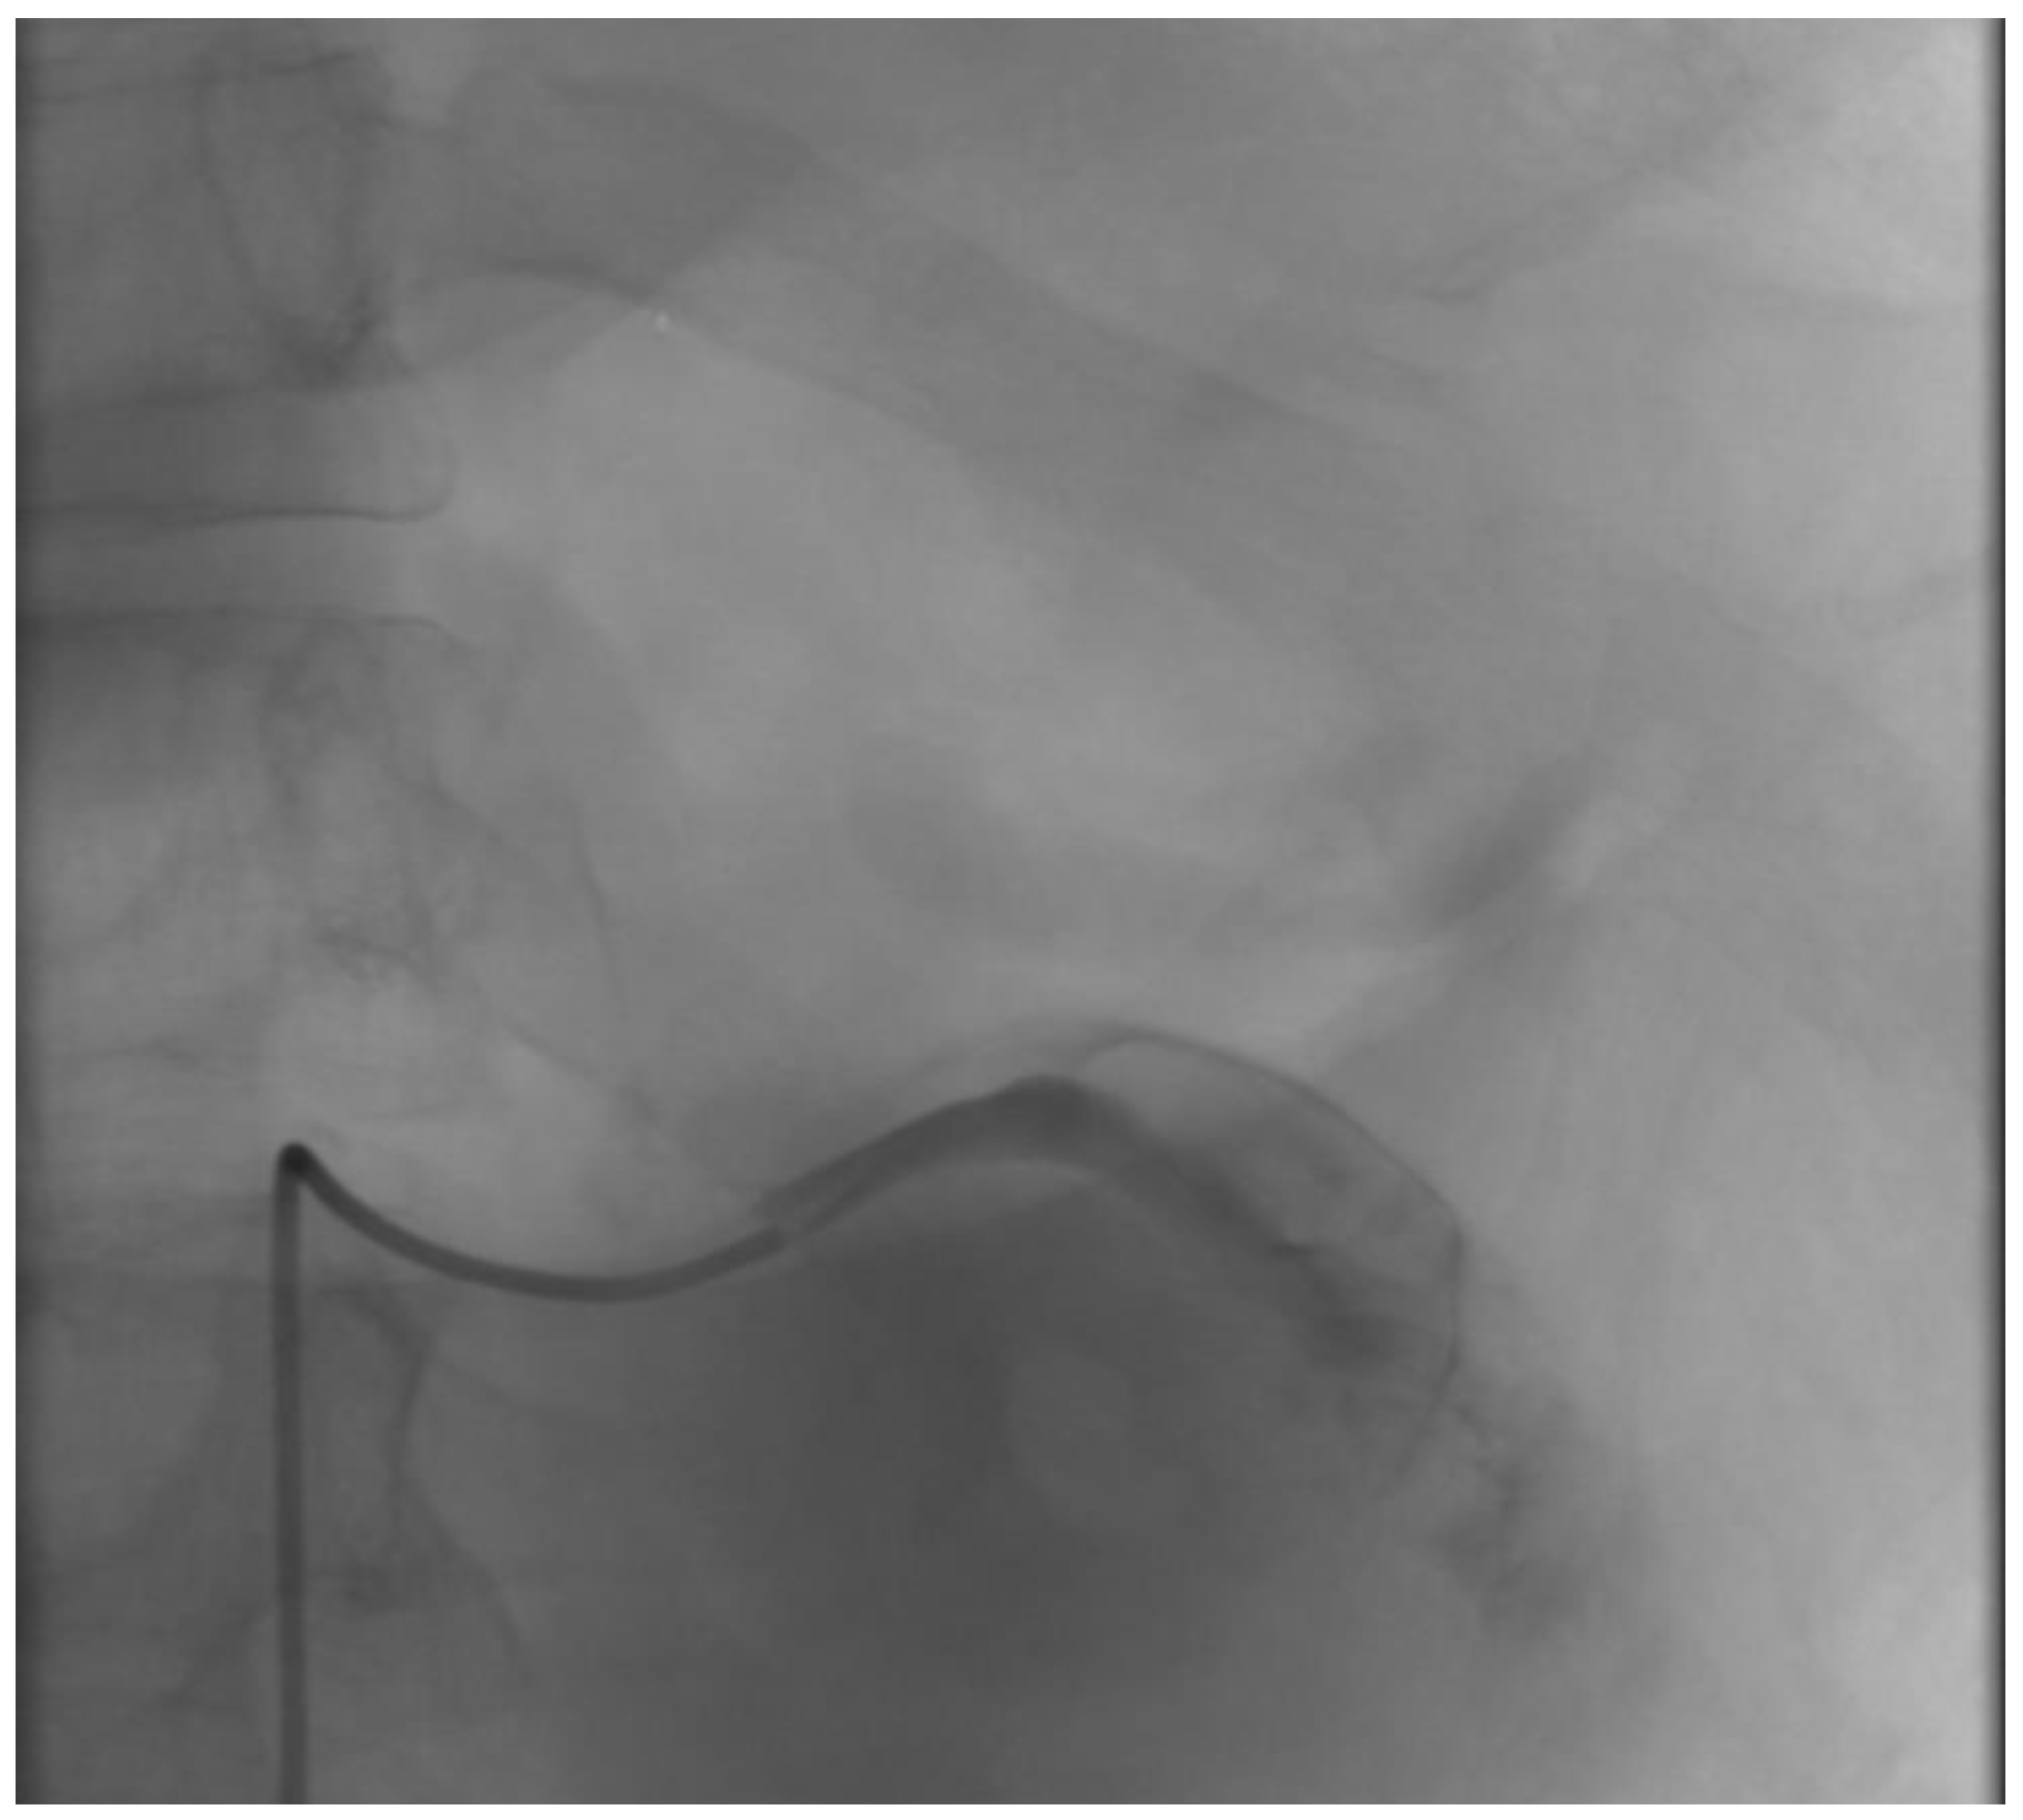

2.1. Case Report